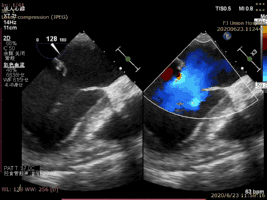

病例2术前二尖瓣反流为重度